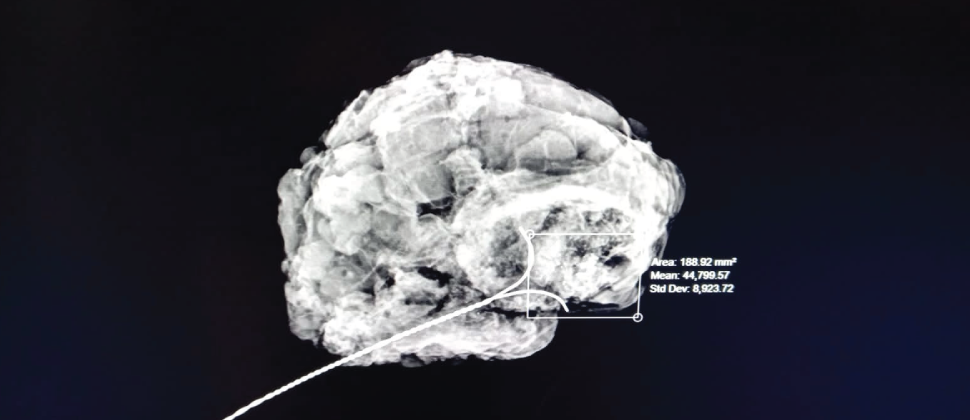

Marcaje de arpón

El estudio consiste en la inserción de una aguja especial en el área específica de la mama donde se localiza la lesión o masa, obteniendo una pequeña muestra del tejido, la cual es enviada a un laboratorio especializado donde se analiza la muestra y se determina la presencia o no de cáncer.

La aguja es insertada por un doctor especializado y certificado guiándose en tiempo real por las imágenes proporcionadas por mastógrafo o por ultrasonido para tomar la muestra exactamente de la lesión o masa. Este procedimiento es de mínima invasión, el cual no requiere hospitalización.